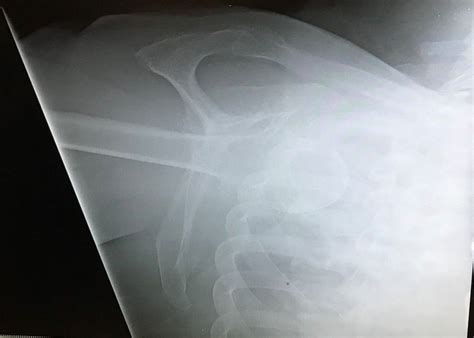

• X-rays: Imaging tests can confirm the dislocation and rule out fractures or other injuries.

• inferior shoulder dislocation xray

• inferior shoulder dislocation xr